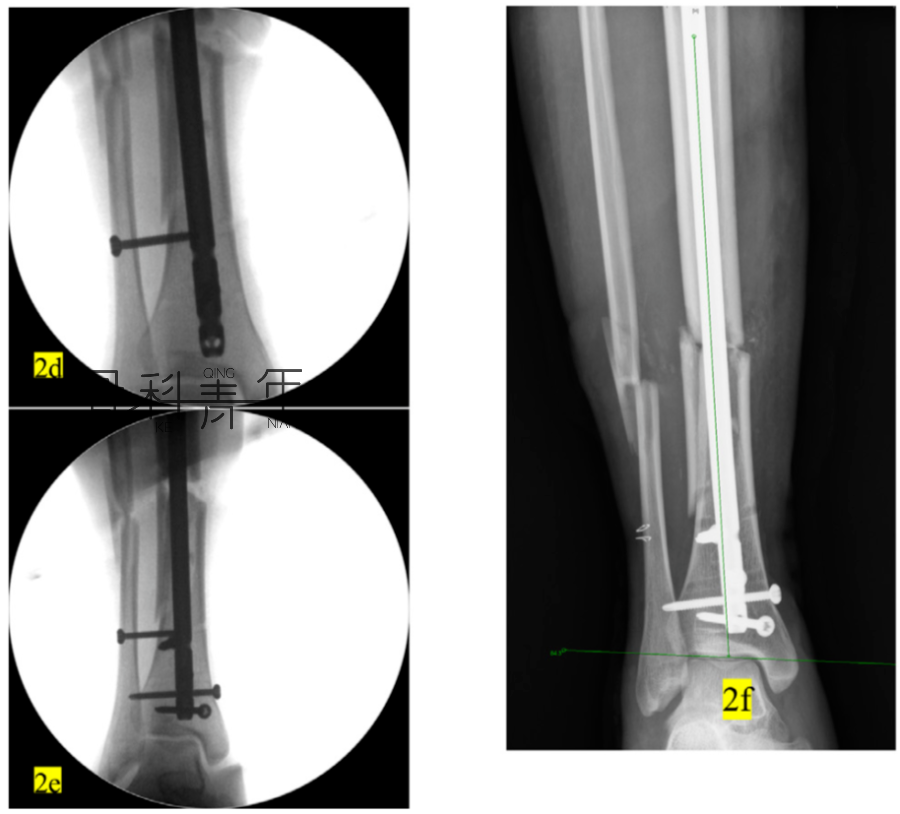

2a-2c:胫腓骨远端骨折,髓内钉固定,主钉插入及远端锁钉锁定后,可见骨折对线不良,存在移位。

2d-2f:依同法在移位平面拧入螺钉纠正移位,恢复对线后置入阻挡钉维持复位。